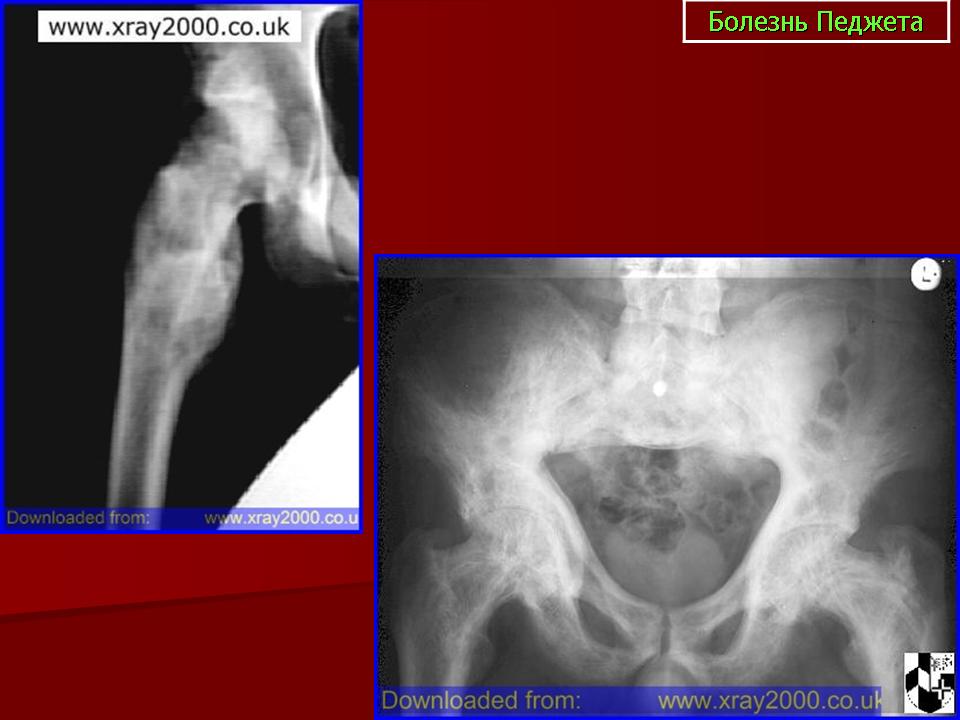

вот,как обещала,рентгенограмма костей таза

p1000728.jpg

Мне кажется, в структуре тазовых костей и бедер преобладает остеосклероз (он метастатический?), на фоне которого видны остеолитические очаги.

По рентгенограмме костей таза по моему мтс и надо смотреть геникологию и молочные железы, при таком процессе основной очаг будет выявлен.

Я тоже склоняюсь к диагнозу миеломной болезни. Рентген черепа бы посмотреть.

Однозначно - тотальное мтс-поражение костей скелета. В анамнезе наверняка рак молочной железы.